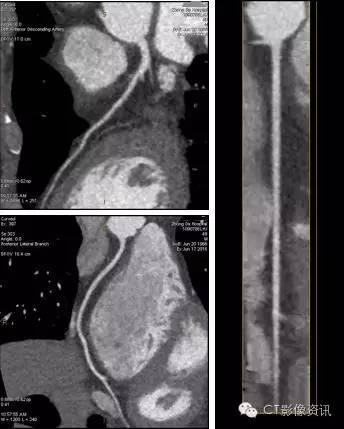

病例2:男性,49岁,BMI值26.4,冠状动脉CT成像与心肌灌注检查,只需一次打药,Revolution即可完成形态学和功能学检查。

CCTA及血管分析如下:

心肌灌注分析如下: